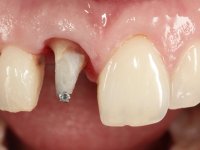

The treatment began with the placement of an intraradicular post and the creation of a new composite resin restoration. This procedure was performed with a surgical approach that allowed the remaining margins to be completely exposed, which were shown to be at a very infra-gingival level. Simultaneously, the periodontal pocket was curetted and root scaling and root planning of adjacent teeth were performed. Two months after this first intervention, the making of the crown began. A pre-print on silicone was performed to make a temporary crown with dual-cured composite resin. Gingival retraction was performed using the technique of kaolin paste compressed by the provisional crown. The impression was made using the double-mix technique with double viscosity with quick-setting silicone. In the laboratory, a crown with a ceramic-coated Zr infrastructure was made. The crown slightly overlapped tooth 12, allowing a dimensionally mimicry of the symmetrical tooth. Its fit was confirmed and approved by the patient; it was definitively cemented with resin-reinforced glass ionomer cement.